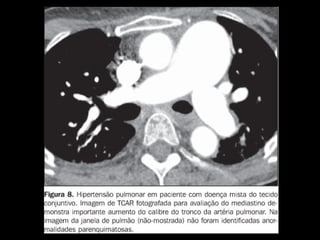

Tomografia computadorizada

Angiotomografia dos vasos pulmonares com TCMD

e reconstruções com filtro de alta resolução;

Mede-se o tronco da pulmonar próximo à sua

bifurcação e lateralmente à aorta ascendente;

Em adultos: até 29 mm;

Sensibilidade: 69-87%;

Especificidade: 89-100%.

Um diâmetro da artéria pulmonar > aorta

ascendente: sensibilidade de 70% e especificidade

de 92% no diagnóstico de HAP;

Achados parenquimatosos: dependem da etiologia

e mecanismo da hipertensão:

Perfusão em mosaico, vidro fosco, espessamento

septal e nódulos centrolobulares.

Derrame ou espessamento pleural, e, em pacientes

com HAP grave, pequeno derrame pericárdico.